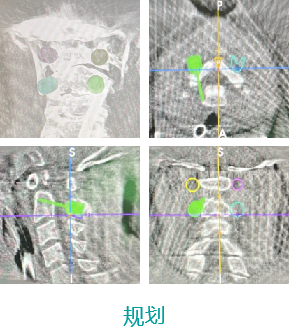

天玑II脊柱手术—颈椎手术

天玑II 辅助颈椎椎弓根螺钉内牢靠术

基本情形:患者男,,,,,49岁,,,,,枢椎骨折

机械人辅助优势:天玑II传承精准智能,,,,,字斟句酌

病例泉源:北京积水潭医院